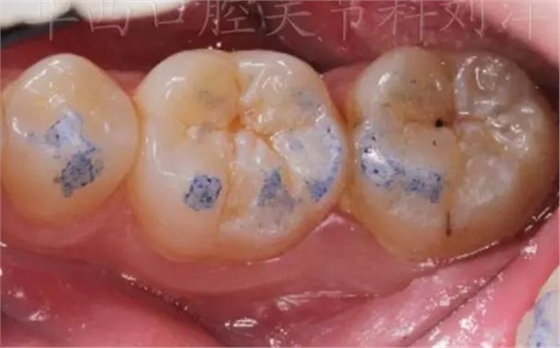

01,牙尖交錯位咬合點

①先用100微米做粗調

▲ 圖1:100µm咬合紙

▲ 圖2:100µm咬合紙的效果